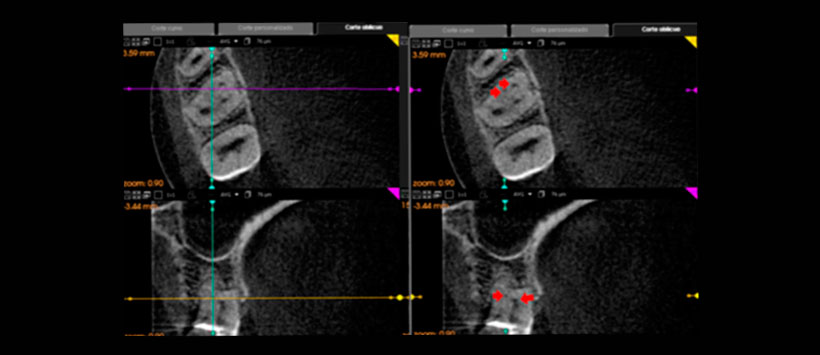

Los objetivos del presente estudio fueron: 1) determinar la incidencia de la configuración apical de los conductos MV1 y MV2 de primeros molares superiores teniendo en cuenta la clasificación II (2-1) y VI (2-2) de Vertucci (Figura 1 Y Figura2); 2) obtener la distancia media entre los orificios MV1 y MV2 a la altura del piso de la cámara pulpar; y c) analizar la relación entre la distancia interorificio y la configuración apical de la raíz MV de primeros molares superiores, en una muestra de población de Colombia.

La hipótesis planteada en el presente estudio supone que a mayor distancia entre los conductos MV1 y MV2 prevalece la configuración 2-1 y a menor distancia prevalece la configuración 2-2. En esta investigación, la validez de esta hipótesis se evaluó mediante un estudio descriptivo que empleó imágenes de CBCT que incluyen primeros molares superiores, para deter- minar la posible relación entre la distancia interorificio MV1-MV2 con la configuración apical en la raíz MV.

Por lo cual se analizó un total de 113 imágenes tomográficas computarizadas de la zona de molares superiores. El análisis consistió en medir la distancia entre los orificios de la raíz MV del primer molar superior a la altura del piso de la cámara pulpar para determinar si hay correlación con el tipo de configuración apical de la raíz MV.